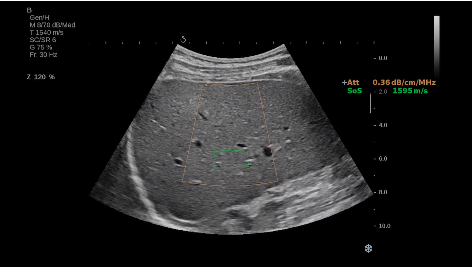

法國(guó)聲科影像(SuperSonic Imagine,SSI. Euroniex:FR0010526814)近日發(fā)表公告,宣布其研發(fā)的新一代“極速”超聲成像平臺(tái)(UltraFast Imaging),首次實(shí)現(xiàn)了肝臟的多項(xiàng)超聲定量評(píng)估新指標(biāo)同步檢測(cè),包括:Att PLUS,SSp PLUS和Vi PLUS等,基本涵蓋肝臟相關(guān)病理變化指征的如纖維化、脂肪變、炎癥等。據(jù)悉,此多項(xiàng)新技術(shù)新將搭載于新Aixplorer系列E超系統(tǒng)。

E超相關(guān)技術(shù)已被多項(xiàng)多中心大樣本研究證實(shí)對(duì)于肝纖維化無(wú)創(chuàng)評(píng)估有重要意義,同時(shí)也可全面應(yīng)用于乳腺、甲狀腺、肝臟、前列腺、肌骨、婦科等全身各組織器官的定量評(píng)估和鑒別診斷。在慢性肝臟方面,聲科E超的肝臟相關(guān)定量診斷技術(shù)集,于2018年獲得美國(guó)FDA認(rèn)證,成為FDA歷史上首次獲批的單病種超聲全面定量解決方案。